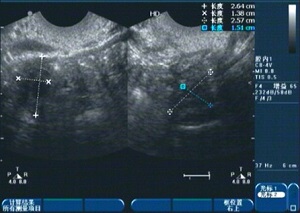

1、診斷:醫(yī)生會(huì)通過詢問病史、體檢及輔助檢查(如超聲檢查、激素檢測等)來確定診斷。